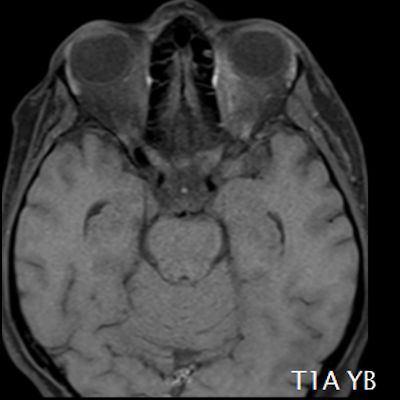

- (B) Orbita MRG’de aksiyel yağ baskılı T1A’da optik sinir prekiazmatik segmenti (oklar) gösterilmiş olup sırası ile aksiyel ve koronal post-kontrast yağ baskılı T1A görüntülerde bilateral optik sinir prekiazmatik segmentte kontrast tutulumu dikkati çekmektedir (oklar ve daire).

- Optik nörit varlığında özellikle optik kiazma ve posterior optik sinir tutulumu görülür ve bilateral olabilir.